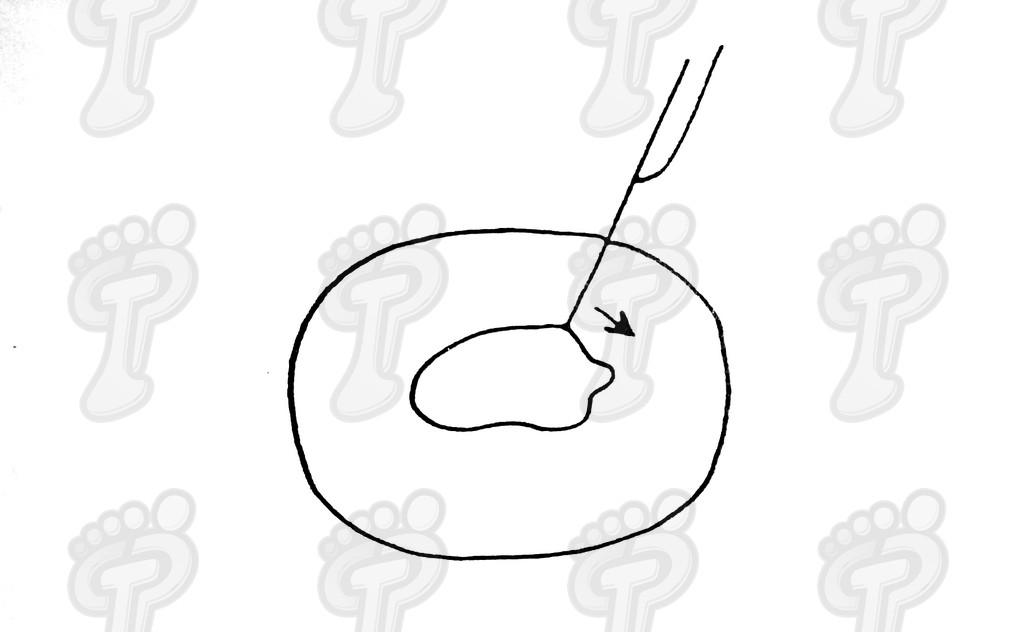

Se realiza la técnica mediante anestesia troncular y sin hemostasia (o al menos, tras el legrado). Hacemos una incisión transversal en la zona dorsoplantar distal a dos o tres milímetros de la prominencia ósea, se introduce el bisturí perpendicularmente al eje de la falange hasta tocar hueso, y a partir de ahí, se desciende bien próximo al tejido ósea para separar partes blandas y delimitar la exóstosis. No se debe incidir lateralmente porque podríamos dañar el paquete neurovascular. Se introduce un cincel separando tejido óseo blando y se delimita la prominencia ósea, la cual suele ser mayor que en la radiografía debido a una zona cartilaginosa radiotransparente. Se legra exhaustivamente con la lima de proximal a distal y de profundidad a superficie (sin vaivén). En las primeras capas (cortical y periostio) notamos que la lima patina y a continuación percibimos el raspado óseo. Con el pulgar de la mano pasiva presionamos de proximal a distal para que salgan al exterior las partículas óseas legradas. Legramos ampliamente ya que al producir un traumatismo óseo siempre hay una regeneración ósea debida a la rica red capilar superficial. Si no lo hacemos así, se puede volver a regenerar el tejido óseo produciendo de nuevo y en poco tiempo la exóstosis. Favorecemos el sangrado de la zona para ayudar a eliminar posibles partículas óseas. Lavamos abundantemente la incisión con suero fisiológico. Volvemos a realizar otra radiografía dorsoplantar intraquirúrgica, a ser posible en la misma posición pre-quirúrgica (la radiografía oblícua no da imagen real del tamaño de exóstosis y la lateral no muestra nada). Hemos de observar en la radiografía que la cabeza de la falange proximal está en el mismo plano que la base de la falange media, ya que si no puede producir algias post-operatorias. Si observamos una nebulosa en la radiografía, son pequeñas partículas o fragmentos óseos que deben drenarse mediante lavados ya que si no se reagrupan y vuelven a regenerar la exóstosis de nuevo. Se han de hacer lavados y radiografías hasta quedar la zona totalmente limpia de fragmentos óseos. Infiltramos anestésico y corticoides en proporción 9 a 1. No hemos de abusar del corticoide porque al entrar en contacto con la trabécula ósea que hemos dejado como capa externa, puede producir problemas graves post-operatorios, tales como la osteoporosis. Se aconseja primero cargar el corticoide y luego el anestésico para evitar que se cristalice el corticoide produciendo trastornos yatrogénicos. Una vez infiltrada la mezcla, presionamos la herida proximal a distal para drenarla ya que sólo nos interesa el efecto farmacológico antiinflamatorio. A continuación, suturamos con seda 5/0 mediante dos puntos simples. En el caso que os mostramos ferulizamos el quinto dedo con una gasa de “U”, impidiendo así la movilización dorsoplantar y, para más sujeción, se une al cuarto dedo con la ayuda de un vendaje circular. Puede impregnarse en yodo la férula en forma de “U” para darle mayor rigidez o consistencia y por lo tanto, menor movilidad al quinto dedo. El vendaje debe ser semicompresivo alineado el dedo. Aconsejamos al paciente reposo durante 48 horas. Pautamos la analgesia correspondiente, y le informamos de las actuaciones que debe efectuar ante determinadas anomalías. Retiramos el apósito quirúrgico a las 48 horas y se cura con povidona yodada dos veces al día (mañana y tarde). Enseñamos al paciente a hacer el vendaje en forma de “U”. A los siete días retiramos la sutura y confeccionamos una cresta de silicona, que debería emplear hasta alcanzar la normalidad articular. Dicha silicona ha de ser utilizada durante un período que oscile entre seis meses a un año.